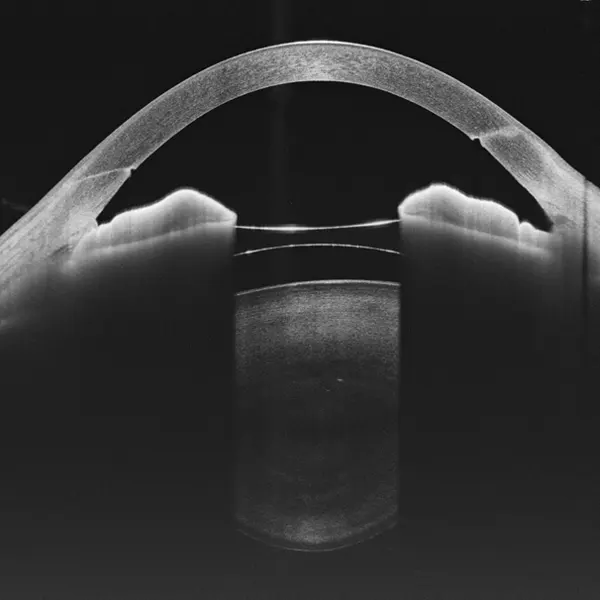

Galería OCTs del TowardPi Yalkaid